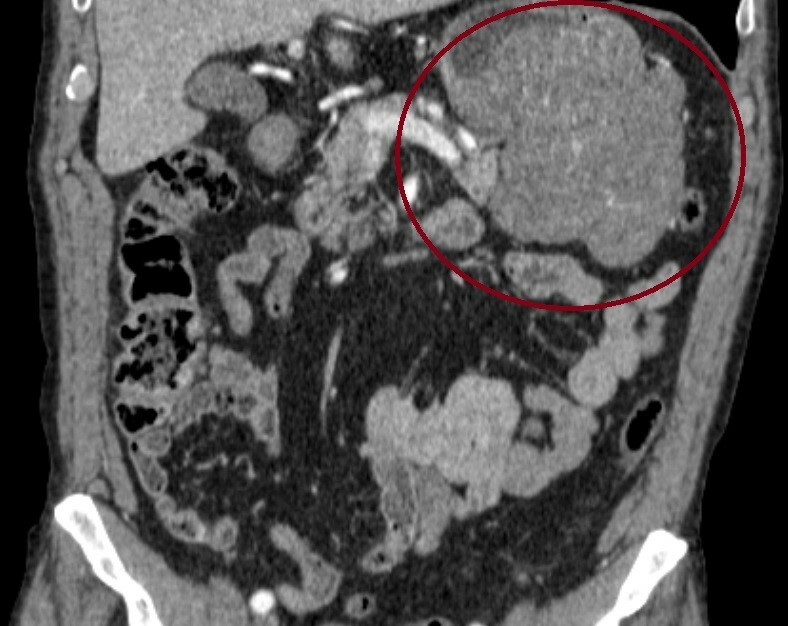

ак Желудка Стадия Фото